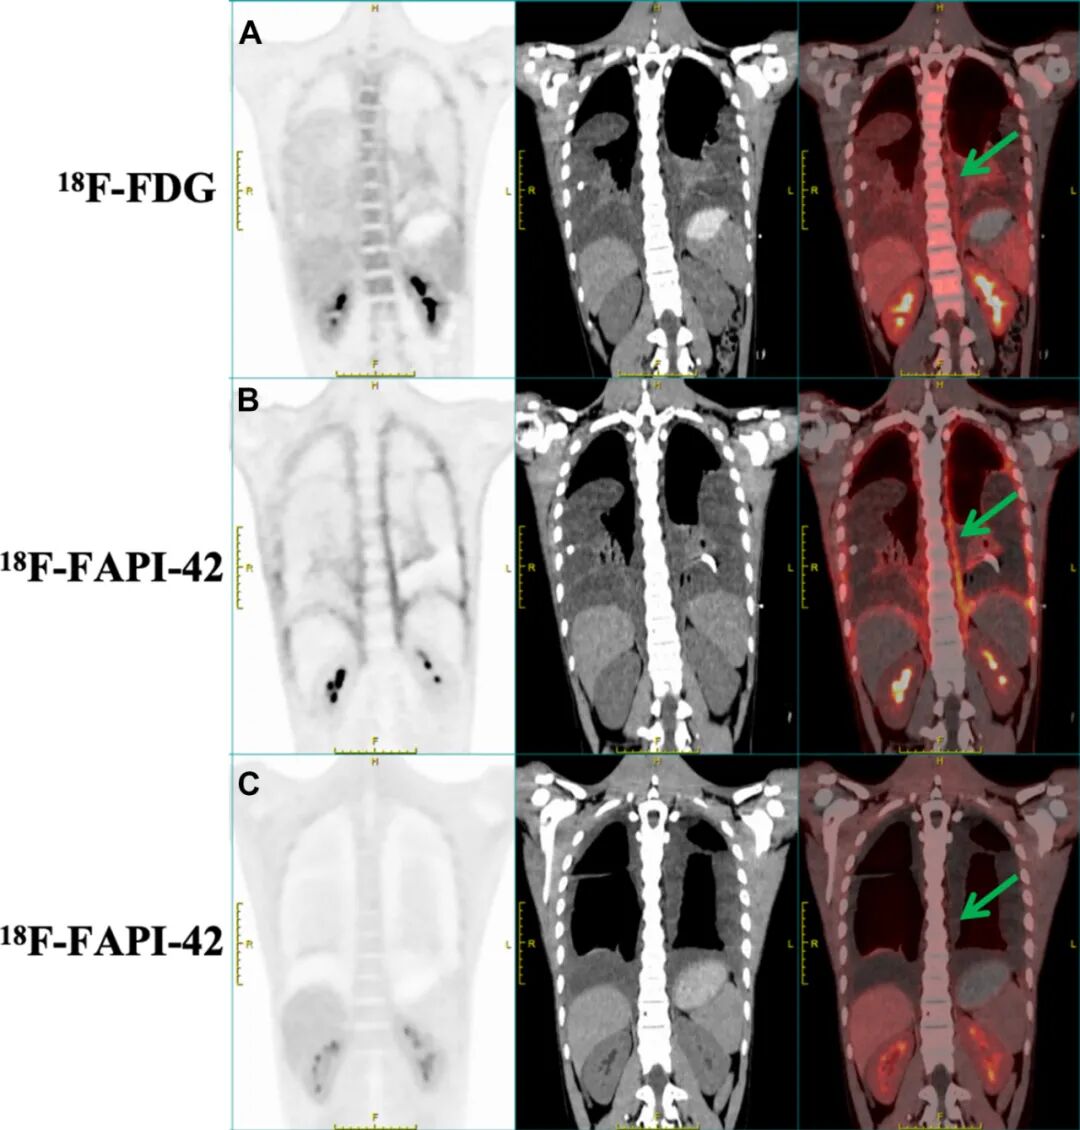

图3. A-C戈勒姆-斯托特综合征患者脊柱的PET/CT影像学表现。A ¹⁸F-FDG PET/CT显像显示脊柱区域示踪剂呈轻度摄取。B ¹⁸F-FAPI-42 PET/CT显像则显示受累脊柱区域的摄取更高。C 经过1年随访评估,¹⁸F-FAPI-42 PET/CT显像显示脊柱区域的示踪剂摄取显著降低。箭头指示示踪剂摄取的特异性区域。¹⁸F-FDG=氟-18氟代脱氧葡萄糖;¹⁸F-FAPI-42=氟-18成纤维细胞活化蛋白抑制剂-42。

治疗12个月后,随访¹⁸F-FAPI-42 PET/CT扫描显示肋骨(SUVmax,2.1)、心包(SUVmax,1.8)和双侧胸膜(SUVmax,2.0)内的放射性示踪剂摄取显著减少,表明成纤维细胞活性受到抑制(图2C和图3C)。胸部超声扫描显示胸腔积液量减少80%,下肢水肿完全消退。重复实验室检查显示CRP(2.1mg/L)和碱性磷酸酶(63U/L)恢复正常,进一步证实了疾病静止。患者在1年随访时已恢复全部学业活动,且报告无功能受限。

2.¹⁸F-FAPI-42 PET/CT成像在检测纤维化活性方面优于传统氟代脱氧葡萄糖成像,可作为诊断和治疗监测的关键工具。